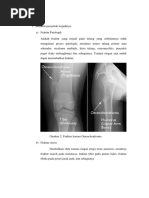

1. Fraktur Colles

Fraktur colles memiliki ciri khas yaitu fraktur radius distal dengan destruksi ,

angulasi, dan displacement ke arah dorsal, disertai pemendekan radial, dan berhubungan

dengan styloid ulnar.